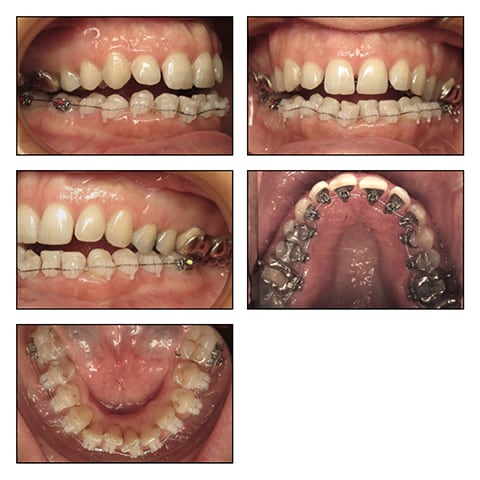

The pre-surgical preparation included a combination of Incognito Brackets and Clarity Advanced Brackets followed by bi-Maxillary surgery. See Figures 3A-E, Figure 3F, Figures 3G-K, Figures 3L-P, Figures 3Q-U, Table 3

During the second phase, the maxillary distraction facilitated orthodontic alignment and transverse coordination without giving rise to major facial changes. Progressively, wire after wire, the bite closed, and there was a spectacular improvement in her breathing pattern with an improved position of the tongue. Her newly-found anatomic equilibrium achieved in the first surgery, stabilized her ventilator function and her swallowing. The shift from oral to nasal breathing was confirmed by the ENT specialist.

The second phase of surgery was not performed as the patient was more concerned by function than esthetics and was happy with the results. She could breathe normally, close the bite and obtain competent lips.